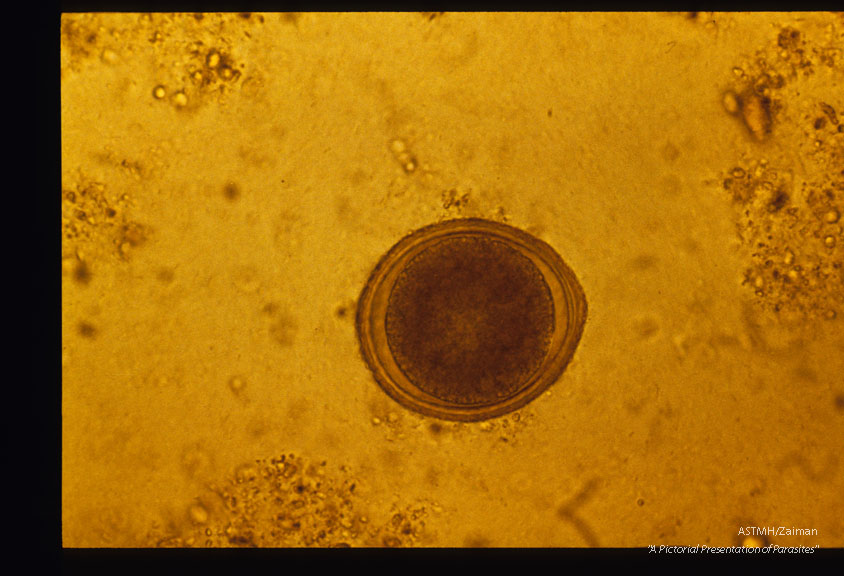

Egg in a dog stool.

Toxocara canis

Description: Egg in a dog stool.